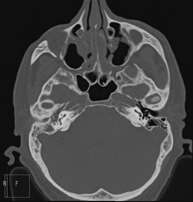

Prova radiològica que consisteix en obtenir imatges del massís facial (cara) d'alta definició anatòmica, mitjançant l'ús d'un equip de TC (Tomografia Computeritzada). Indicacions: tumors, cirurgia plàstica. - TC Oïda

Prova radiològica que consisteix en obtenir imatges de la oïda d'alta definició anatòmica, (conducte auditiu intern i extern, timpà, ossets de l'oïda) mitjançant l'ús d'un equip de TC (Tomografia Computeritzada). Indicacions: trastorns de l'audició, quadres vertiginosos, mareigs, acúfens (xiulets). - TC Dental

Prova radiològica que consisteix en obtenir imatges dels sins paranasals d'alta definició anatòmica, mitjançant l'ús d'un equip de TC (Tomografia Computeritzada). Indicacions: cefalea, tos crònica, mucositat, infeccions facials. - TC Penyal

Prova radiològica que consisteix en obtenir imatges de l'os penyal del temporal (oïda interna, mitjana i externa) d'alta definició anatòmica, mitjançant l'ús d'un equip de TC (Tomografia Computeritzada). Indicacions: pèrdua d'audició sobtada o crònica, quadres vertiginosos, mareig, malformacions congènites. - Angio-TC Troncs Supraaòrtics